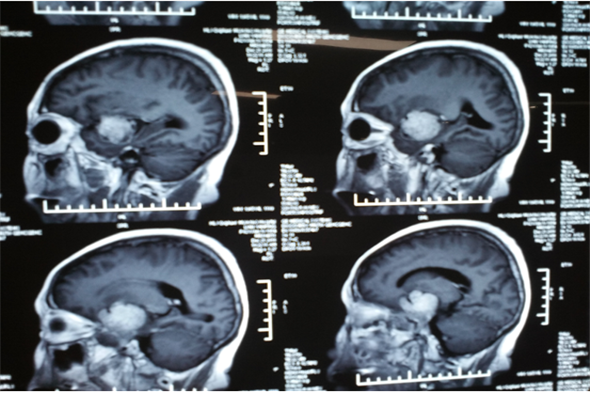

廉女士现年62岁,既往有垂体瘤病史1年左右,随着肿瘤的不断长大,出现精神症状,有言语迟钝及行动受限等表现。患者曾因此病周转于周边各大医院,后了解到我院成功治疗多例此类疾病,治疗效果良好,遂慕名来到我院治疗。由吴卫东主任及科室成员共同诊治,进行头部核磁,显示蝶鞍、蝶窦及左侧鞍旁占位性病变,增强见肿瘤强化明显,直径大于5.0cm,诊断为侵袭性垂体瘤。吴卫东主任带领科室成员共同讨论商议,制定出详细的治疗方案,并做好术前准备,开启了又一次充满挑战的手术治疗。

当日,先由麻醉医生为患者麻醉,在手术室护士的密切配合下,由吴卫东主任为患者施行手术,术中吴卫东主任凭借精湛的手术技能,在开颅切除蝶骨脊旁5.0cm肿瘤后,在狭小的动脉与各个神经缝隙间精细操作,以刮匙完全刮除鞍内肿瘤,保留周边血管及神经,手术进行的十分成功,在术后的第一天患者就意识清醒,无功能缺失。

垂体瘤在临床出现症状较多,主要是肢端肥大,巨人症及库欣氏综合征,亦可出现泌乳或性功能低下等症状,垂体瘤从形态上可分为:微腺瘤、大腺瘤、巨大腺瘤。超过3cm即为巨大腺瘤,该患者肿瘤直径为5cm,为巨大腺瘤。其周围为颈内动脉,视神经及动眼神经等重要组织结构,手术风险较大,神经外二科成立以来垂体瘤切除术已是常规手术,但此巨大垂体瘤实属罕见。吴卫东主任精准的判断及娴熟的手术技巧,神经外二科团队及麻醉科快速、高效的配合再一次创造了奇迹。

术前头部MRI